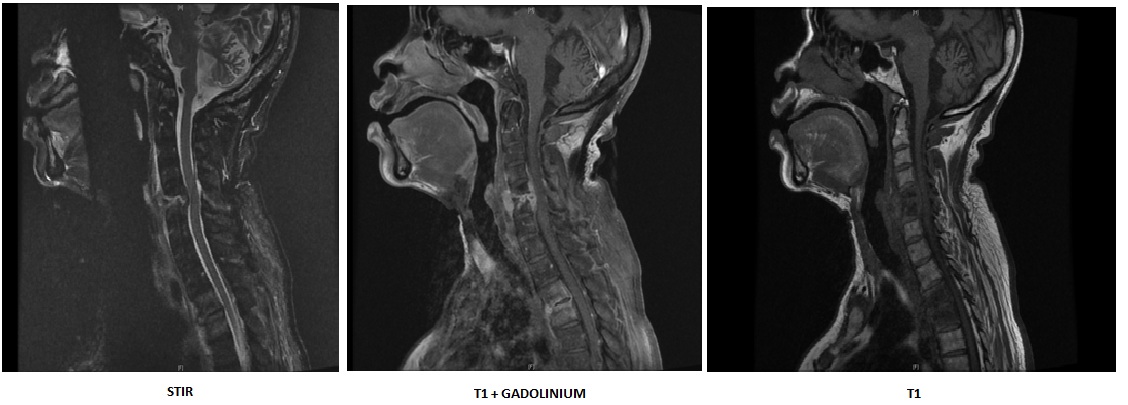

Spondylodiscite multifocale du rachis cervical et du rachis dorsal